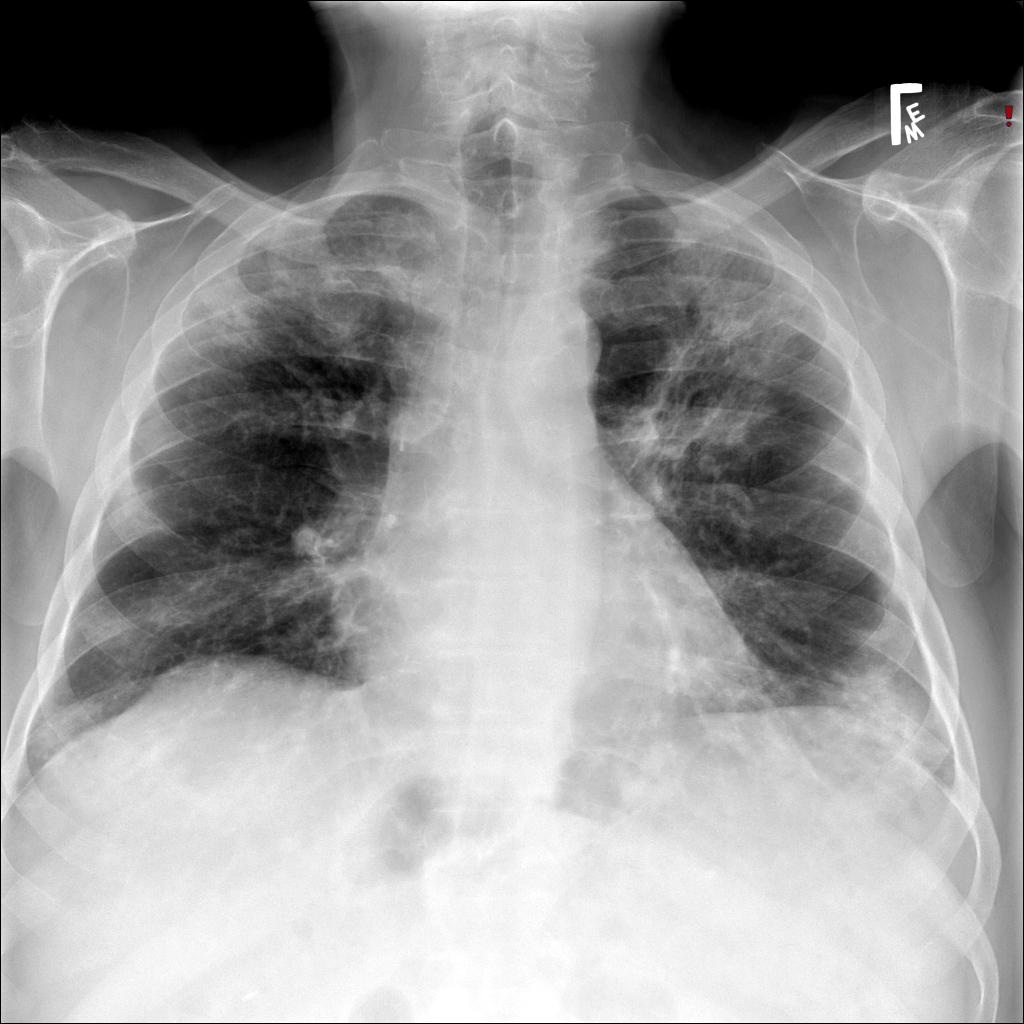

In our patient, the chest radiograph revealed multifocal alveolar infiltrates predominantly in the right upper lobe, left upper lobe, and left lower lobe. Chest CT revealed patchy ground glass and consolidative infiltrates throughout both lungs.